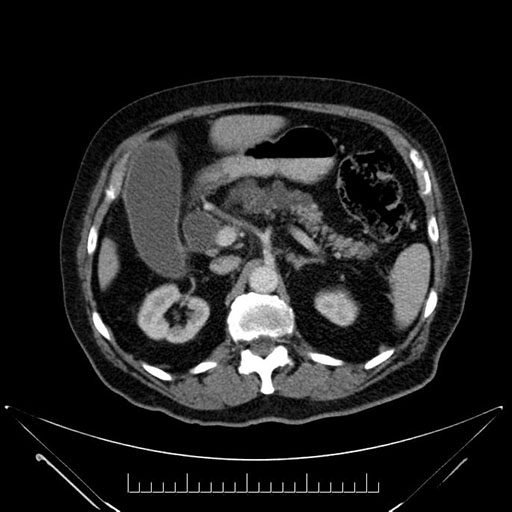

Imaging Analysis

Look through the patient's CT scan to identify any areas of concern for the necessary procedure.

Based on your CT findings, which issue(s) would give reason for "planned slowing down moment(s)" in this case?

Considering a standard Whipple procedure, what step(s) of the operation would you do differently in this case?